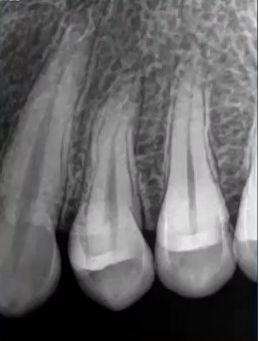

32岁,男性,因咬物不适来院就诊。

查:14残根,牙龈红肿;35叩诊(+),45叩诊(+),牙颌面见畸形中央尖。

35叩诊(+)

二次拍根尖片确认可看到根尖低密度炎症,临床检查与影像学检查相符,是根尖周炎。

曲面断层片怎么看口腔精读 | 一次性教你看懂曲面断层片!_https://www.jmylbn.com_新闻资讯_第21张